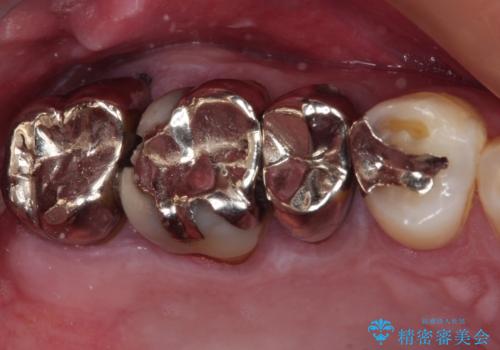

以前治療した歯が続々とむし歯に 全顎むし歯治療